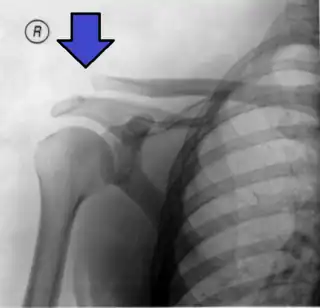

![]() Radiografía de un hombro dislocado, modificada para mostrar los huesos, apreciándose una clara separación entre el extremo de la clavícula y la escápula. | ||